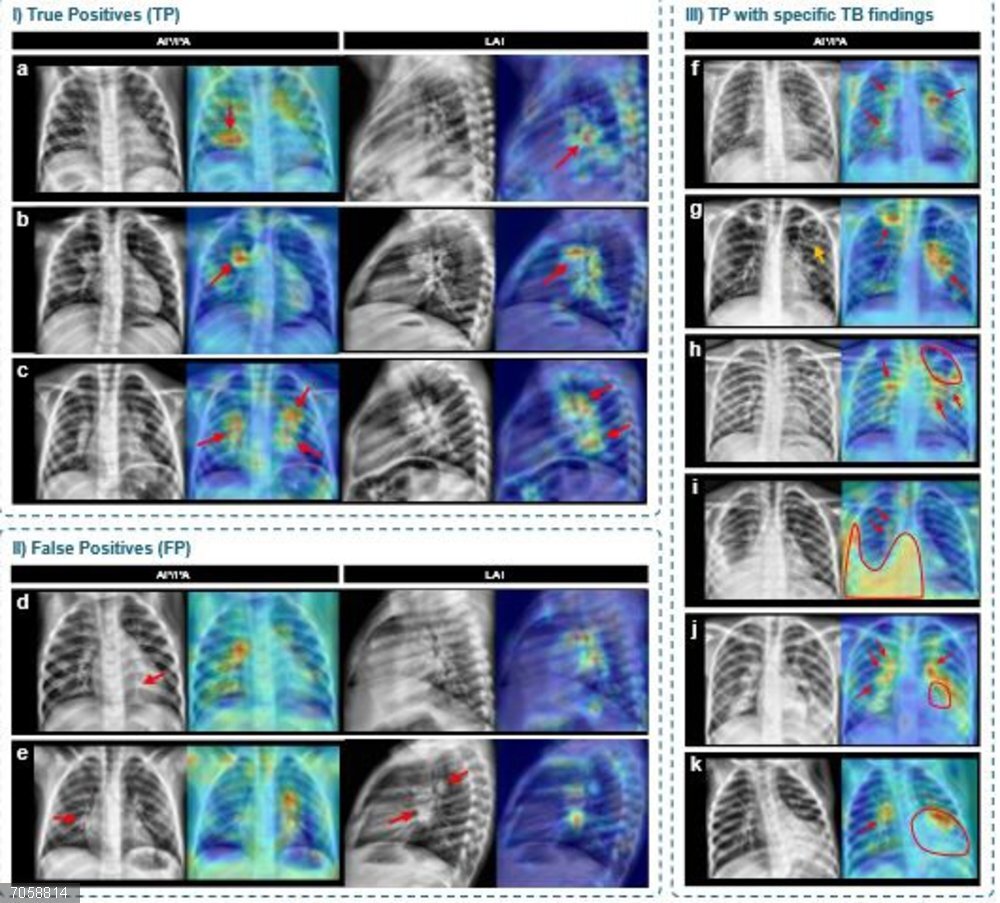

Mapas de activación generados mediante técnicas de explicabilidad que señalan las regiones de interés utilizadas por el modelo para tomar sus decisiones sobre las radiografías